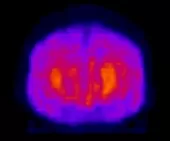

Сцинтиграфия головного мозга

ОФЭКТ/КТ - производится оценка регионального мозгового кровотока при инсультах, эпилепсии, преходящих ишемических атаках, психических заболеваниях, при травмах головы.

Перед исследованием пациенту вводится радиофармпрепарат. Из крови радиоизотоп сначала проникает в эндотелий измененных сосудов головного мозга, а затем – в интерстициальное пространство патологического участка с дальнейшим внутриклеточным накоплением в очаге поражения. Далее осуществляется запись и анализ радионуклидного исследования (сцинтиграфии или ОФЭКТ/КТ).